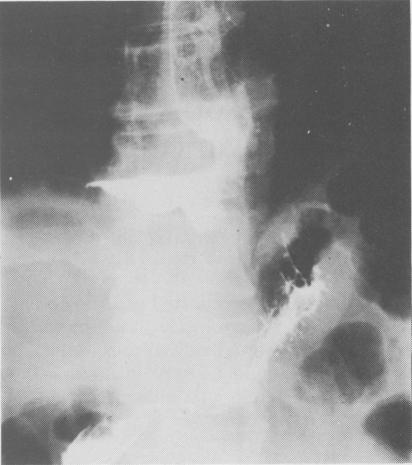

A case is reported of delayed broncho-oesophageal fistula presenting several weeks after fibreoptic injection sclerotherapy for oesophageal varices in a patient with chronic active hepatitis who eventually died from bronchopneumonia. Such serious complications of injection sclerotherapy should be kept in mind with the increasing popularity of this method of early treatment of bleeding oesophageal varices.

本文报告了一例延迟性支气管食管瘘的病例。该患者患有慢性活动性肝炎,在接受食管静脉曲张的纤维内镜注射硬化治疗数周后出现了这种情况,最终死于支气管肺炎。随着这种早期治疗食管静脉曲张出血方法的日益普及,应牢记注射硬化治疗的此类严重并发症。